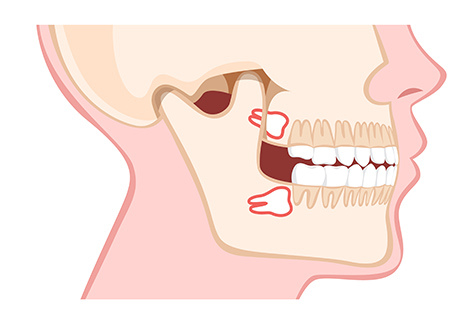

親知らずとは一番奥(前から数えて8番目)に生えてくる歯です。親知らずはむし歯の原因になる場合もありますので、気になっている方は一度受診していただき抜歯の必要があるかを診断しましょう。

隣の歯を圧迫している状態です。むし歯などのお口のトラブルが起こりやすく、かみ合わせや歯並びに影響が出る場合もあるので、抜歯をおすすめします。

完全に歯ぐきの中で横向きにはえている状態です。

抜歯するためには、歯ぐきを切開してめくりあげ、歯の頭の部分と骨の一部分を削り取り、分割しながら抜歯していきます。